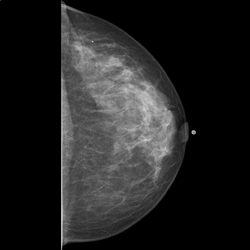

Digitale Mammographie

Jede 10. Frau erkrankt heute an Brustkrebs. Die Brustdiagnostik besteht aus der digitalen Mammographie inklusive Tomosynthese (3D Mammographie im Schichtverfahren), der Sonographie (Ultraschall) und der Mamma-MRT (Kernspintomographie).

Hierbei stellt die Mammographie das wichtigste Vorsorgeverfahren zur Früherkennung dar. Der Ultraschall der Brust ist eine ergänzende Methode zum Beispiel zur Differenzierung bestimmter Strukturen und kann die Mammographie nicht ersetzen.

Um eine hohe Bildqualität bei möglichst geringer Dosis zu erreichen, arbeiten wir digital. Durch den Einsatz einer modernen, digitalen Vollfeld- Mammographie liegt die effektive Dosis nur noch bei 0,1-0,3 mSv.

Zahlreiche Studien konnten aufzeigen, dass der Nutzen, Brustkrebs frühzeitig entdecken zu können, viel höher ist als das Risiko, durch die Mammographie an Krebs zu erkranken.

Die digitale Tomosynthese ist ein neues ergänzendes Verfahren zur Brustkrebsdiagnostik und eine Weiterentwicklung der Mammographie. Es werden im Gegensatz zur herkömmlichen digitalen Mammographie eine Serie von Schichtaufnahmen erzeugt, die eine überlagerungsfreie dreidimensionale Darstellung der Brust ermöglicht.

Die Strahlenbelastung liegt nur wenig oberhalb der konventionellen Mammographie.

Die Mammasonographie ist eine ultrahochauflösende Ultraschalluntersuchung der Brust und erfolgt ggf. am selben Termin.

Mit diesem Verfahren können Tumore, Zysten oder Entzündungen der Brust untersucht werden.

Frau PD Dr. Hermle ist von der Kassenärztliche Vereinigung Bayern für die Mamma-MRT zertifiziert. Diese strahlungsfreie Untersuchung liefert in ausgewählten Fällen eine Zusatzinformation über das Kontrastmittelverhalten von suspekten Läsionen.

Die Praxis ist entsprechend den KV-Richtlinien zertifiziert.

Empfehlung:

Basismammographie ab 40. Lebensjahr

Kontrollen alle 2 Jahre

Risikopatientinnen jährliche Kontrollen